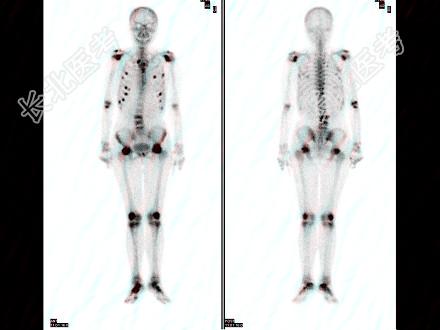

- 多项选择题女性,72岁, 双下肢间歇性钝痛3个月,现行走困难, SCr256μmol/L,HGB68g/L, 骨显像最可能的诊断是 ( )

A、双侧股骨头缺血性坏死

B、多发的骨转移癌

C、多发性骨髓瘤

D、腰椎有病理性压缩

E、肋骨浓聚点全部是骨质破坏